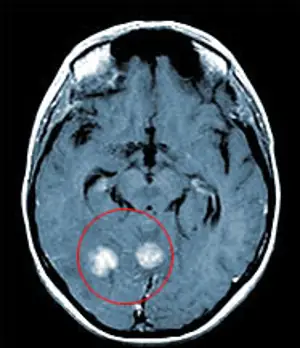

Лечение метастазов рака легкого в головном мозгу кибер-ножом

МРТ-изображение с двумя метастазами рака легкого в головной мозг

Оба метастаза были удалены за один сеанс, длительностью 1 час. На снимке результат контрольного обследования через 4 месяца после лечения. Обе опухоли были удалены, после лечения пациент в тот же день вернулся к работе